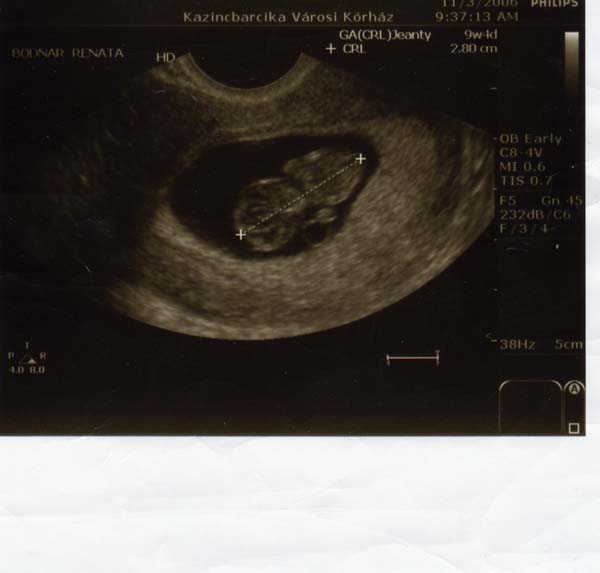

Én most írok először. 14 hetesek vagyunk / még az elején tartunk/. Nagyon szépek a képeitek, aranyosak a babák. Megpróbálok betenni én is 2 hépet a picimről, az egyiken 9, a másikon 12 hetes.

Üdv.: Andi Kép Kép